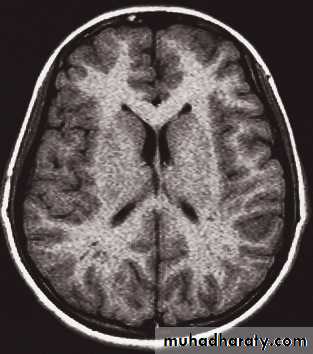

MRI of the brain

• Axial, coronal and sagittal projections are all considered standard• T1-weighted and T2-weighted images.

• It is possible to recognize flowing blood and, therefore, the larger arteries and veins stand out clearly without the need for contrast medium.

• The characteristics of grey and white matter are different, and both are clearly different from the CSF in the ventricular system and subarachnoid space.

• The disadvantages of MRI compared with CT are the inability to show calcification, lack of bone detail, the relative expense of the technique, and the difficulty of monitoring seriously ill patients

• IV contrast in T1 WI

• MRA and MRV, Recent advances of MRI: perfusion, diffusion, spectroscopy, functional MRI, and tractography